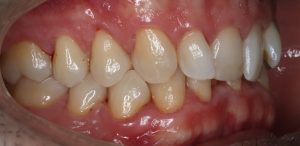

FULL

35 Semanas de tratamiento